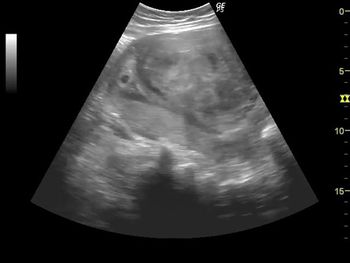

Challenge your diagnostic skills. What's your diagnosis based on these abdominal images of a late second trimester fetus?